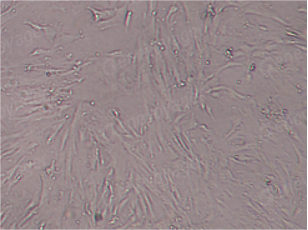

宠物间充质干细胞(Mesenchymal Stem Cells, MSCs)是一种具有自我更新和多向分化潜能的成体干细胞。劲帆生物医药科技(武汉)有限公司拥有成熟的干细胞分离及制备技术,可以分离多种组织来源的间充质干细胞;同时提供与宠物疾病相关的基因修饰的工具病毒载体,如慢病毒、腺病毒、腺相关病毒等。团队现已开发出多种来源的间充质干细胞,其中包括针对炎症性肠病、口炎、哮喘、关节炎等通用型干细胞以及涉及宠物关节炎、干眼症、骨再生、心肌病、脊髓损伤、大面积皮肤缺损、衰老等病症的专病专用的基因修饰的间充质干细胞。

间充质干细胞(MSCs)是存在于机体间质组织中的成体干细胞,由于具有强大的自我更新能力、多向分化潜能和旁分泌的作用,能够通过调节全身功能的方式恢复机体的内环境稳态,已成为近年来宠物临床疾病治疗的研究热点。间充质干细胞存在于全身结缔组织中,已从不同组织(如骨髓、脂肪组织、外周血、肌肉、牙髓、牙周韧带、关节软骨、骨膜)和胚外组织(如脐带血、膜和羊水)中分离出来。在体内或体外适宜条件下能够分化为多种细胞类型,包括成骨细胞、软骨细胞、肌肉细胞、脂肪细胞等。

目前大多数犬、猫临床试验使用的间充质干细胞主要为骨髓间充质干细胞( BMSCs)、脂肪间充质干细胞( ADMSCs)和脐带血来源间充质干细胞( UCBMSCs)。在兽医学中,MSC主要从脂肪组织和骨髓中获得。BMSCs是间充质干细胞的丰富来源,但具侵入性,需要更年轻的供体,因此脂肪组织成为首选。

拥有成熟的干细胞分离制备技术,可以实现多种属、多组织来源的间充质干细胞的分离制备。目前有大鼠脂肪间充质干细胞、小鼠脂肪间充质干细胞、人源脐带间充质干细胞等。